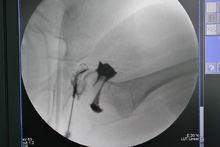

2.6月齡到18月齡患兒

對該年齡段患兒,髖關節的半脫位或脫位應當通過閉合復位或切開復位進行治療,並將其作為首選治療方式,對於髖臼發育不良者可以採用支具治療。閉合復位必須在基礎麻醉下進行,術中關節造影顯示復位滿意且穩定,則給予人類位石膏固定,要求髖關節屈曲在100~110°,外展不能超過60°,過度外展的石膏和支具固定容易造成股骨頭缺血壞死;如果閉合復位不滿意或不穩定,則需要做髖關節切開復位,一般做單純髖關節切開復位加人類位石膏固定;石膏固定後在手術室透視了解髖關節復位情況。出院前複查髖關節正位片,必要時做CT或MRI檢查了解復位情況。出院後的部分複查可採用超聲檢查,以減少X線檢查次數。通常石膏固定3個月左右後再更換支具固定3個月左右。閉合或切開復位後髖臼發育的潛力很大,可以持續到復位後的4~8年,多數DDH患兒不需要二次做髖臼或股骨手術。

發育性髖關節發育不良術中關節造影

發育性髖關節發育不良雙側髖關節人類位石膏固定